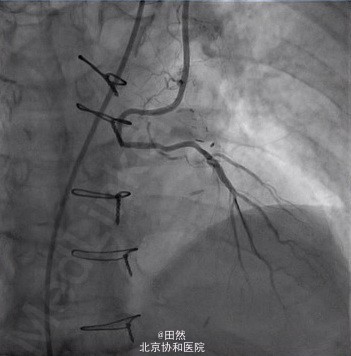

CABG术后桥血管-自体血管吻合口再狭窄 PCI成功

病例一 王XX,M/82, 主诉:间断心悸发作18年,发作性胸闷1年,加重3天 现病史: 1996年夏天无诱因反复出现心悸发作 1998-8-4无诱因出现心悸、烦躁、心前区不适,自服硝酸甘油症状持续2h无缓解,急诊心电图示“房颤,心室率约140次/分,V2导联ST段抬高明显”,急诊CAG:左主干狭窄75%,回旋支近中段50~80%狭窄,前降支管壁不规则,右冠50%狭窄。 1998-8-24行冠脉搭桥手术(取双侧桡动脉、术中搭桥RIMA- RCA、LIMA-LAD、AO-LRA-OM1、AO-RRA-OM2)。术后恢复良好。 患者3天前无诱因出现胸闷,持续0.5~2小时,活动耐量较前略下降,平地行走约500米需休息。 PMH:高血压病40余年,血压最高170/100mmHg,现规律口服络活喜、倍他乐克、单硝酸异山梨酯缓释片、阿司匹林,血压控制平稳,在135/60mmHg。 个人、婚育及家族史无殊。 PE:心率58次/分,律齐,各瓣膜区可闻及II/6级吹风样收缩期杂音,以主动脉瓣听诊区最响。双侧桡动脉搏动正常、对称,双侧足背动脉搏动正常、对称。余无殊。 病例二 赵XX,F/60 主诉:间断胸闷气短3年,再发伴胸痛3月 现病史: 2011年始出现活动后胸闷、气短,休息后或口服速效救心丸后可缓解,多发于劳累、遇冷及饱餐后。 2013年10月较前加重,性质同前,发作频繁,静息及夜间均有发作,每日5-6次。ECHO:左房增大,左室松弛功能减低,EF56%。 2013-11-4行CAG:LM远段局限狭窄70%,LAD开口及近中段狭窄70%,远段可见对冲血流。LCX开口及近段局限狭窄最重90%,OM1近段局限狭窄最重70%。RCA近中段100%闭塞。 2013-11-13行CABG术(AO-SV1-RCA,LIMA-LAD,AO- SV2-OM1),手术顺利,术后恢复良好。 术后1-2月未再发作活动后胸闷、气短,近3月前开始出现活动后胸痛,可放射至后背及上肢,伴胸闷、气短,持续数分钟,休息或含服硝酸甘油3-4分钟后可缓解。 PMH:高血压14年,血压最高达160/100mmHg。2型糖尿病15年,现应用胰岛素及降糖药物治疗,空腹血糖可控制在7-8mmol/L,餐后2h血糖在13-16mmol/L左右。发现血脂高10余年,未规律控制。

1、CABG术后心肌缺血复发率大约在4-8%,Lambert等的研究显示随访7.5年CABG术后有20%的患者 发生不稳定性心绞痛或非ST抬高型心肌梗死,RITA试验中CABG 术后1年严重心绞痛发生率约5%。CABG术后再缺血原因包括:桥血管病变(桥血管狭窄、“string”现象),自体血管病变的进展及再血管化不全(搭桥近端的狭窄逐渐闭塞、自体血管血流竞争不过桥血管、未搭桥的自体血管原有病变加重或发生新的病变)。 2、SVG vs IMA vs RA孰优孰劣? Shah等对CABG术后1607例心绞痛复发患者行造影检查,其平均复查时间间期99 个月,静脉桥的病变率为39%。左乳内动脉发生病变的机会明显低于静脉桥,文献报道结果14.1-29%不等。动脉桥的10年通畅率明显高于静脉桥85% vs 61%。Umesh等研究显示随访565±511天,桡动脉桥的通畅率低于IMA和SVG(51.3%vs90.3%和64.0%,P<0.002)。 3、桥血管病变的原因 术后早期1个月以内心肌缺血的主要原因是IMA吻合口狭窄,1年以内主要与静脉桥血管狭窄和闭塞有关,1年和5年以后则绝大多数缘于静脉桥的闭塞。 4、左乳内动脉吻合口狭窄的原因 主要与术中技术原因有关,如术中损伤血管内膜导致急性血栓形成、移植血管过长扭曲或过短牵拉 不适当的吻合口位置、选择自体血管过细等。 5、CABG术后再次介入治疗的问题 主要困难:病变程度严重,比如慢性闭塞或严重的弥漫性狭窄病变,因此介入治疗的技术成功率相对较低,导丝不易通过病变。 主要的并发症为:远端血管栓塞导致无复流或慢血流 远期疗效: 介入治疗的局限性是支架内再狭窄和再次血管重建,裸支架治疗SVG病变的再狭窄率为20-53%。药物洗脱支架是否能够明显降低桥血管支架再狭窄的发生存在争议。 (本病例由北京协和医院沈珠军教授团队提供)